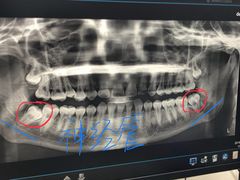

• 西安交通大学口腔医院(主院区)

• -西安交通大学口腔医院(主院区)